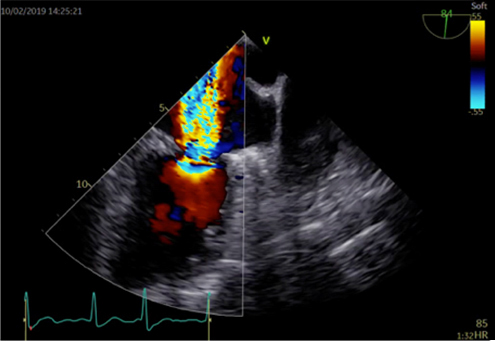

心エコー検査

心エコー検査は、超音波検査とも呼ばれ、胸に小さな機器(プローブ)を当てるだけでリアルタイムに心臓の動きの度合い、大きさ、さらには弁逆流などを診断することができます。最近は3D技術も導入され、より詳細な情報を得ることができるようになりました。

経食道心エコー検査

経食道心エコーは胃カメラとよく似た検査ですが、胃を見るわけではありません。胃カメラと同じような長い管を飲み込んでいただき、超音波を使って食道からすぐ隣の心臓の中を詳細に観察する検査です。心臓の中の構造やサイズが非常に細かくわかるので、この検査でなければ診断がつかない疾患もあります。3D技術がもっとも威力を発揮する検査です。